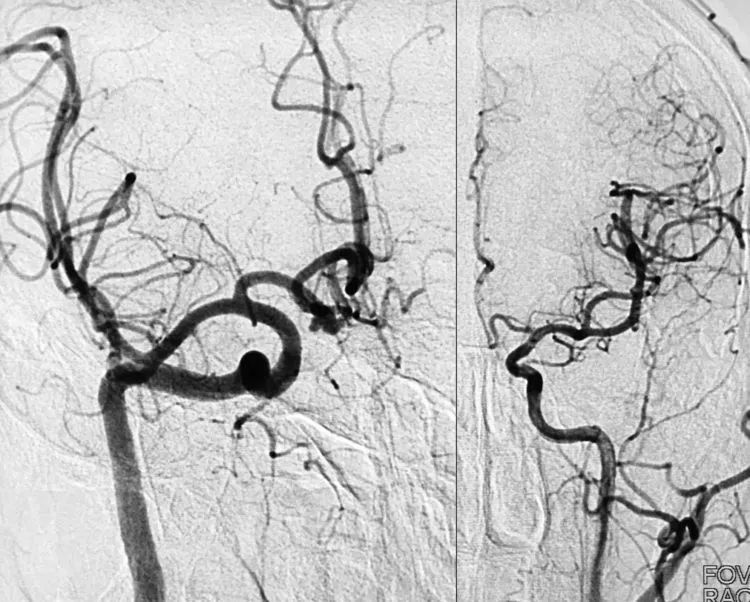

2017年4月5日行DSA+介入治疗。右颈内动脉造影显示右侧前交通动脉瘤,呈牛角形分叶(左图);左颈内动脉造影显示左侧大脑前动脉A1段发育稍差(右图)。拟行双微管技术栓塞,无须刻意保全前交通动脉。

右颈内动脉造影三维重建测量,公共瘤颈宽3.0 mm;大分叶3.4 mm×5.8 mm,可作为小型动脉瘤对待;小分叶2.3 mm×2.4 mm,可作为微小动脉瘤对待。